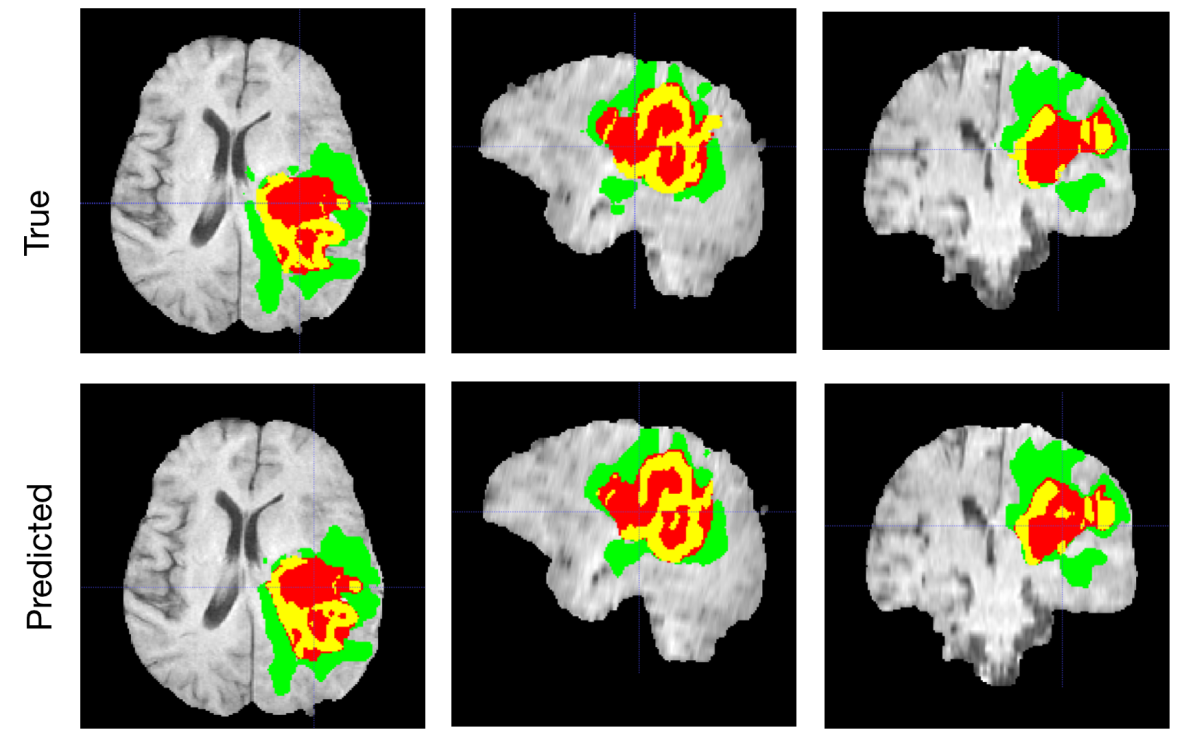

Typically, the output result, even of a single model, is accurate as shown in Figure 1, however several cases still remain segmented imprecisely. Figure 2 shows an example of an incorrectly over-segmented whole tumor (WT) region, which is spilled over on the right side of the brain, most likely because the underlying MRI (Flair) has substantially higher intensity values in that region. More variability in training examples might have helped to solve the issue, or integration of anatomical knowledge of e.g. ”symmetrical highlights around ventricles are unlikely to be a tumor” , but such information is rather complicated to put inside of the network.